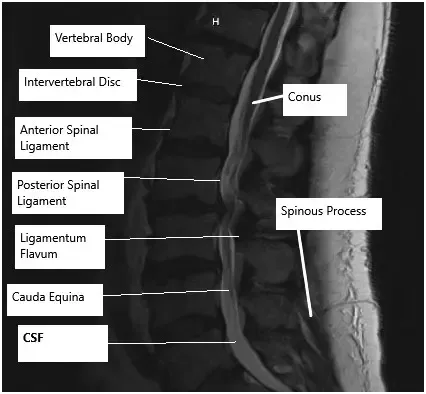

How the Body Part Normally Works? (Relevant Anatomy)

The lumbar spine consists of five vertebrae that support the lower back and allow for movement and flexibility. Between these vertebrae are intervertebral discs that act as cushions, absorbing shock. Nerve roots extend from the spinal cord through openings between the vertebrae. When discs bulge, herniate, or degrade, they can press on these nerves, causing pain, numbness, and weakness.